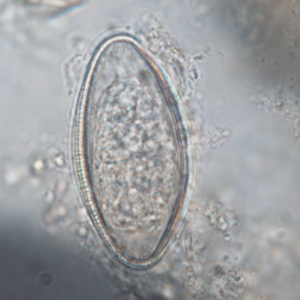

Oesophagostomum eggs are typical strongyle eggs. It is impossible to differentiate species of Oesophagostomum morphologically. Coproculture is required in order to refine the diagnosis (Cogswell, 2007).

Differential diagnosis includes Ternidens deminutus eggs, and to a larger extent, any non-embryonated strongyle eggs (Cogswell, 2007).